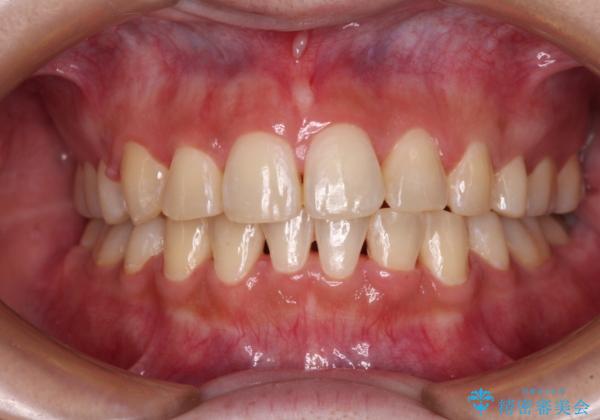

- 八重歯やデコボコをインビザラインで治療したいとのことで来院された患者様です。

インビザライン単体で治療を行うには叢生が強いと判断されたため、事前にワイヤー装置で抜歯矯正を行い、ある程度改善してからインビザラインにて仕上げていくこととしました。